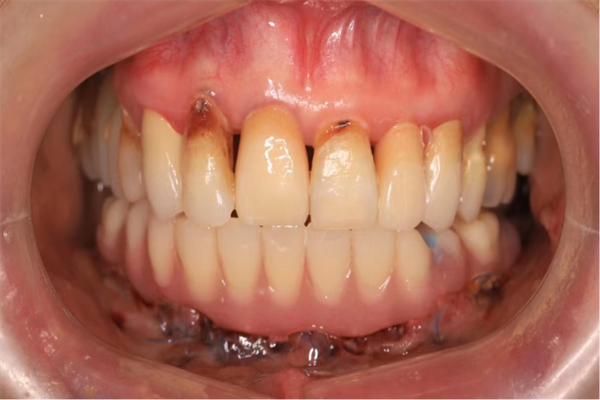

過渡義齒即刻戴牙(告別拔牙后缺牙期)

“數(shù)字化全口種植牙”目前在經(jīng)濟發(fā)達(dá)地區(qū)開展較多,由于其難度大、設(shè)備要求高、技術(shù)依賴性大,陜西省開展較少。此手術(shù)的獨立開展意義重大,標(biāo)志著西電集團(tuán)醫(yī)院口腔科種植修復(fù)達(dá)到國內(nèi)先進(jìn)水平。

數(shù)字化全口種植牙的技術(shù)優(yōu)勢因即刻種植+3D數(shù)值化導(dǎo)板的引導(dǎo),術(shù)中創(chuàng)傷小,精準(zhǔn)度高,且無拔牙等待鑲牙時間,與傳統(tǒng)種植方式相比,大大縮短了手術(shù)時間,減小了手術(shù)創(chuàng)傷,減少了患者身體及精神負(fù)擔(dān)。